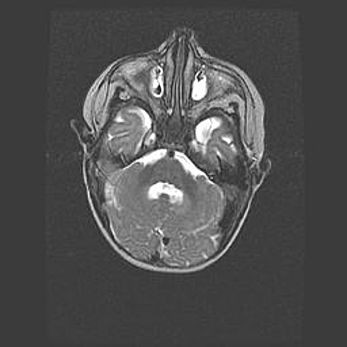

Подострая гематома правой гемисферы мозжечка.

Наружная гидроцефалия.

Возраст: 15 дней

Вес: 3100 г

Пол: женский

Окружность головы: 37 см

Срок гестации: 35-36 недель

При открытой наружной форме гидроцефалии у новорожденных расширяются и переполняются субарахноидные пространства.

Кровоизлияния в мозжечок имеют две клинико-анатомические формы: полушарные гематомы и кровоизлияния в червь.

К появлению этой патологии может привести: повреждения головного мозга, возникающие в результате асфиксии и гипоксии плода при беременности, или травмы во время родов. Редко гематома мозжечка может быть результатом первичной коагулопатии и сосудистой мальформации, диссеминированном внутрисосудистом свертывании, изоиммунной тромбоцитопении.